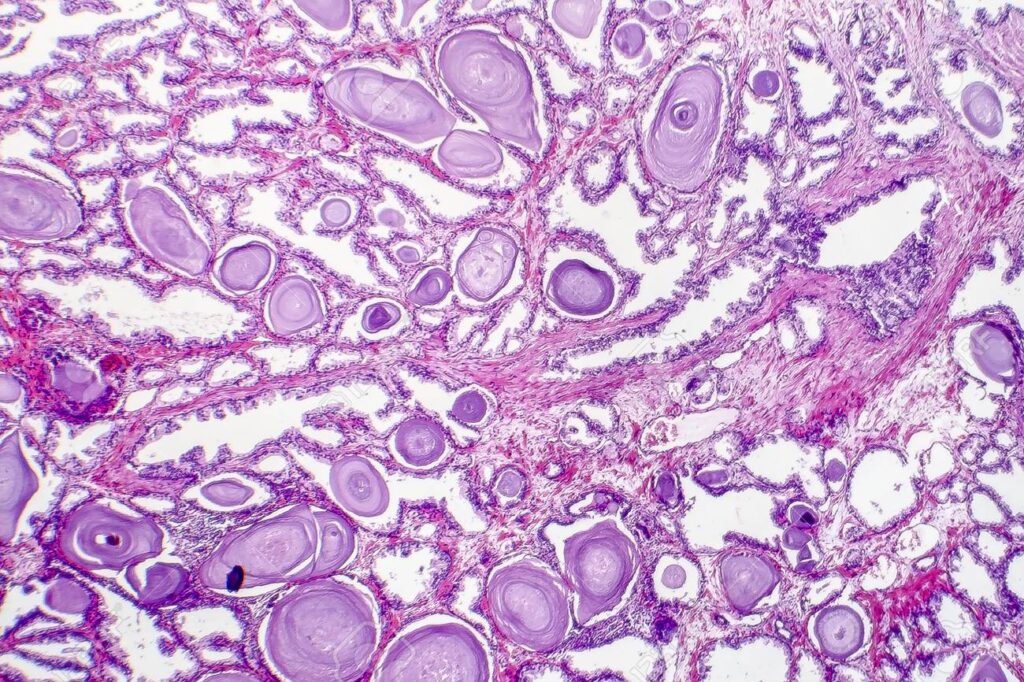

En el análisis microscópico de la próstata afectada por HBP, se evidencian nódulos hiperplásicos en el corte transversal, mostrando variaciones en color y consistencia, características determinadas por su contenido celular.

La diferenciación entre nódulos glándulares y estromales revela peculiaridades distintivas. Los nódulos predominantemente glandulares exhiben un tono amarillo rosado, una textura blanda y la capacidad de secretar un líquido prostático blanco lechoso. En contraste, aquellos compuestos principalmente por estroma fibromuscular presentan un color gris pálido y una consistencia más dura.

A nivel microscópico, cada nódulo individual contiene glándulas que varían en tamaño, desde pequeñas hasta grandes o quísticamente dilatadas. Estas glándulas están separadas por células del estroma fusiformes y aparentemente inofensivas.

Las glándulas, en su estructura más íntima, están revestidas por dos capas celulares distintas. Una capa interna compuesta por células secretoras cilíndricas y una capa externa de epitelio basal cúbico o aplanado. La conformación de las glándulas puede generar una arquitectura papilar.

En situaciones donde las glándulas han experimentado un notable aumento en tamaño, la afectación del suministro vascular puede resultar en infartos prostáticos. Estos infartos, a su vez, pueden asociarse con áreas adyacentes de metaplasia escamosa, indicando alteraciones morfológicas adicionales.